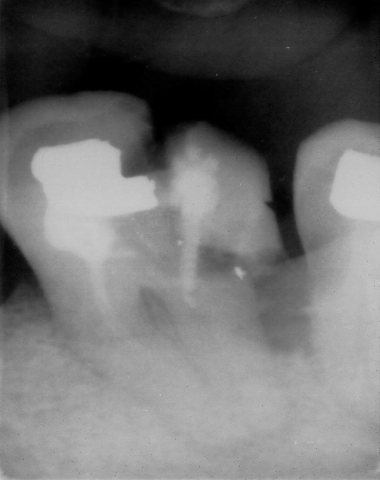

enfin le document tant attendu--------------------dans le compagnonnage on appelle cela un chef d'oeuvre( "d'architecture" bien sur)--ceci prouve que l'on peut se passer d'obturation canalaire,alors à quoi cela sert une nouvelle convention ?---un petit truc pour les non initiés:avec un thrombone c'est possible aussi ---un autre truc vous séparez les 2 racines et vous avez 2 sc33 , qui dis mieux ? Allez je lance un grand concours de photos dans le meme style ---les dentistes conseil peuvent y participer, of course

belle reconstitution et a priori très solide puisque c'est la dernière dent de l'arcade à être en place

En tout cas, peterpan, ta photo est bien passée, youpee, et tu as gardé ton flegme devant une certaine forme de bizuthage typiquement eugenolienne!!!. Bon la dent.... sans retraitement et avec le petit liseré vertical qu'on voit entre les deux racines, et la limite osseuse qui a connu des jours bien meilleurs , je pense que la photo sur eugenol aura une plus grande longévité.

Et, mode sérieux on; tu as le droit de coter une hémisection et un retraitement pour une même dent, mais pas deux sc33, interdit, forbidden zone!!!

adhoc je te remercie pour tout ce que tu fais pour moi ,par contre je ne suis pas tout a fait d'accord avec toi sur les 2 sc33, je pense que cela est tout a fait possible . Cela ressemble a une 46 au départ,imagine un instant, après la séparation de racine, une migration distale de 44 et 45 ,cela s'est déja vu meme sans ortho. Je te le dis c'est imparable. j'attends l'avis des ------"spécialistes"----Jespère n'avoir vexé personne ce coup ci .Bien le bonjour de clochette : très contente de l'effet que vous faites sur peter----------Tiens en vla une autre (de radio)----surlécutant , comme disais l'autre---là malheureusement séparation de racine impossible,par contre, encore une fois économie de bio ,mais petit "rattrapage" par extraction ,attendons le joli mois de mai: dc16 je crois avec la nouvelle convention, c'est fou ce qu'on peut prolonger avec les antibio......